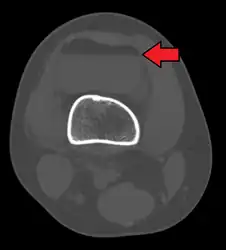

In all injuries to the tibial plateau radiographs (commonly called x-rays) are imperative. Computed tomography scans are not always necessary but are sometimes critical for evaluating degree of fracture and determining a treatment plan that would not be possible with plain radiographs.[6] Magnetic Resonance images are the diagnositic modality of choice when meniscal, ligamentous and soft tissue injuries are suspected.[7][8] CT angiography should be considered if there is alteration of the distal pulses or concern about arterial injury.

3D reconstruction of a CT image of a tibial plateau fracture